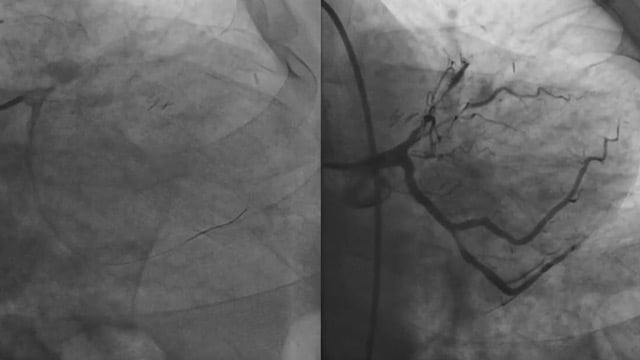

Challenging PCI scenarios after CABG

10 Dec 2025 – From GulfPCR-GIM 2025

This session addresses the complexities of PCI in post-CABG patients, focusing on the application of intravascular imaging and functional assessment to guide strategy. It discusses clinical and anatomical factors influencing the choice between native vessel and graft PCI, and explores management techniques for unyielding graft lesions,...